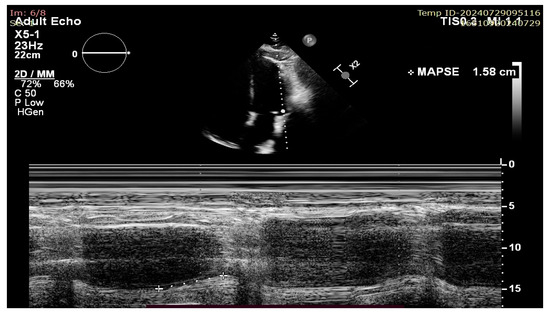

Mitral Annular Plane Systolic Excursion (MAPSE): A Review of a Simple and Forgotten Parameter for Assessing Left Ventricle Function